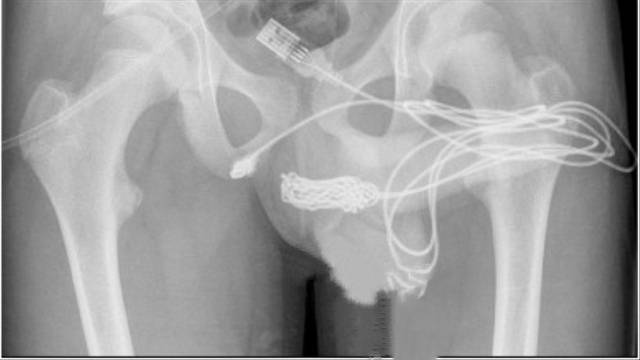

Kabel USB yang nyangkut di penis pasien. Foto: Loufopoulos, et.al, Urology Case Report, 2021

Selanjutnya, para dokter di Rumah Sakit University College London menggunakan sinar-X untuk memastikan "posisi dan bentuk yang tepat dari simpul yang diformat.? Pasien lalu dibawa ke ruang operasi.